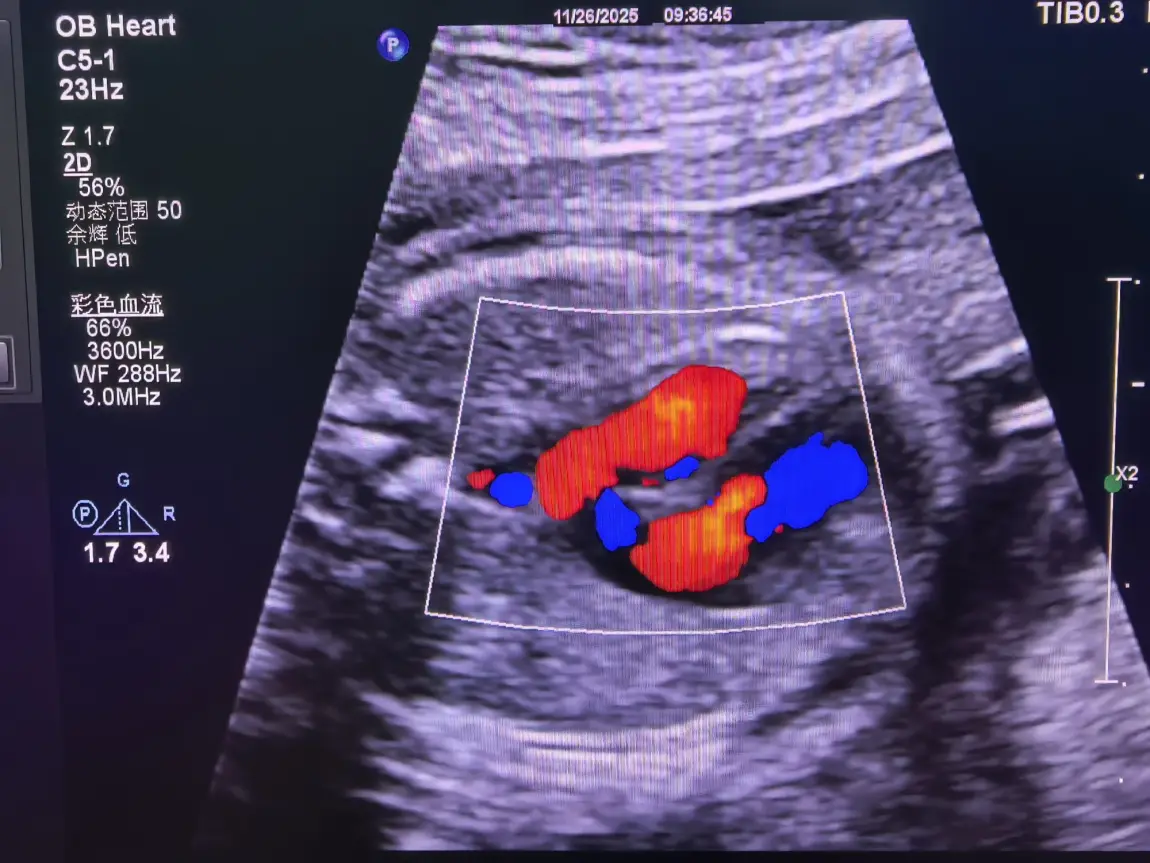

作为超声科医生,诊室里的超声屏从清晨亮到下午,屏幕上脏器的轮廓、血流的走向,容不得半点马虎,每一次探头移动都要精准对准毫米级的细节。一整天下来,神经始终绷得紧紧的,直到脱下白大褂,指尖触到小鹏P7+温润的车门把手,那份职业带来的沉重才慢慢卸下。遇上值夜班,忙到深夜走出医院,浑身疲惫得连开车的力气都没有,我便躺在副驾座椅,裹着车内的静谧睡上一小会儿,这短暂的休憩,足以驱散通宵的倦意。